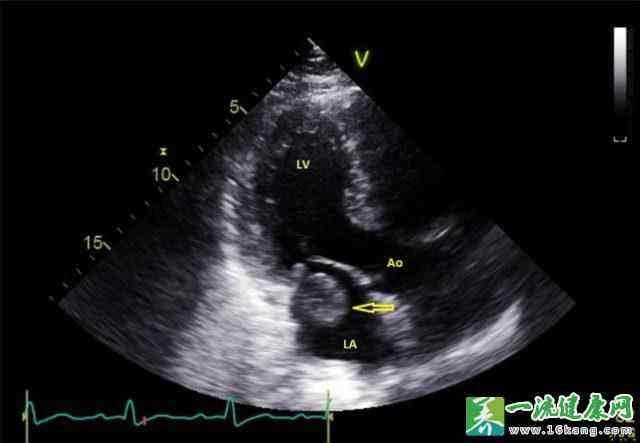

▲ 图6 彩超下左心房血栓

肢体动脉栓塞治疗的关键在于预防,对于房颤、风湿性心脏病、心肌梗死室壁瘤病人,最重要的是预防措施,就是口服抗凝、抗血小板聚集药物,比如阿司匹林、华法林、利伐沙班等药物,防止心脏内血栓形成,另外需要定期复查心脏彩超,筛查有无血栓情况。